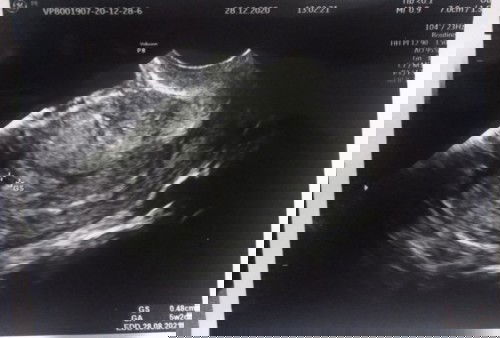

Ibu2 mau tny, hamil 5w tp baru terlihat kantung kehamilan dgn uk sekian normal/tidak? Terimakasih bu

Hamil 5 week